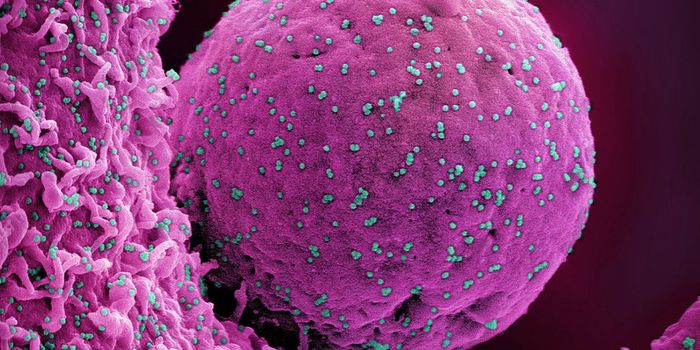

SEP 08, 2024MicrobiologySARS-CoV-2, the pandemic virus that causes COVID-19, has mutated endlessly since it burst on the scene in late 2019. An ...

AUG 27, 2024MicrobiologySince the start of the COVID-19 pandemic, the virus that causes the illness - SARS-CoV-2 - has had a practically infinit ...